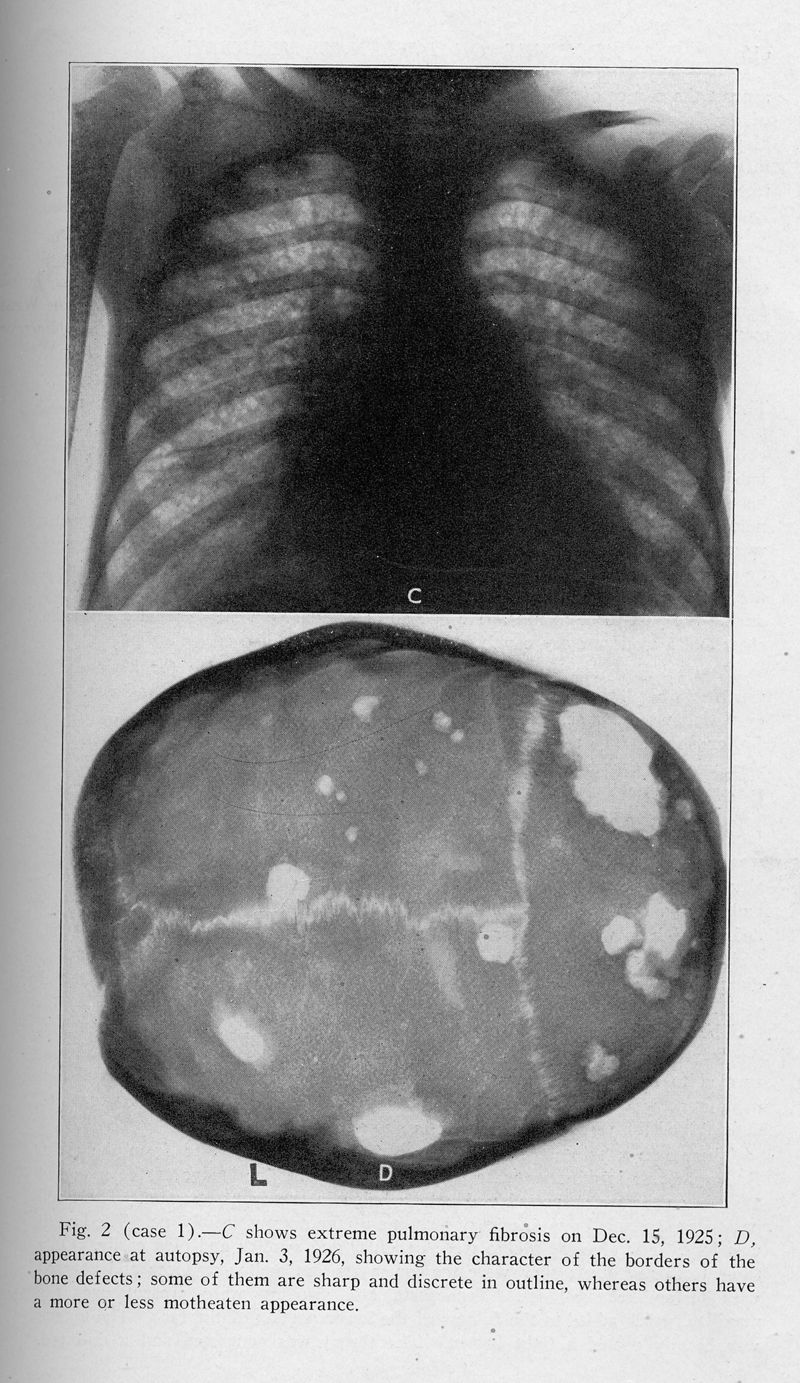

Xanthomatosis and the reticuloendothelial system. Correlation of an unidentified group of cases described as defects in membranous bones, exophthalmos and diabetes insipidus (Christian's syndrome)

In : Archives of internal medicine (1908), 1928, Vol. 42, pp. 611-74